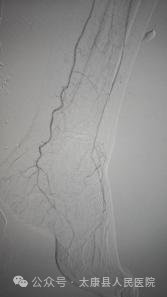

术后造影

面对挑战,介入血管外科团队迅速启动多学科会诊(心内科、肾内科、ICU),结合CTA影像精准评估,制定个体化手术方案。术中采用"双向穿刺+内膜下血管成形+血栓清除+支架置入"等技术,在DSA精准引导下,仅通过大腿1个针眼大小的切口,成功开通闭塞血管:减容后股浅动脉置入支架,足部PPL弓显影,溃疡区染色,血供恢复。手术全程2小时,出血量不足10毫升,术后患者下肢血流即刻恢复,疼痛感消失。